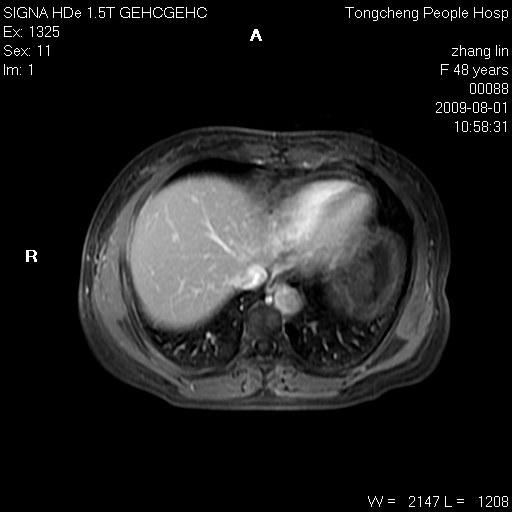

女,48岁。健康体检,彩超发现右肾占位性病变。平素健康。

临床诊断:右肾占位性病变,性质待定(囊肿?肿瘤?)。

上中腹部mr平扫+增强扫描,图像如下:

右肾上极见一类圆形病灶,t1wi呈等信号t2wi呈等高混杂信号,三期增强无强化,边界清---考虑囊肿出血。

同反相位均表现为等信号,病变无强化,考虑含蛋白的囊肿可能,弥散加权相或许有些帮助,